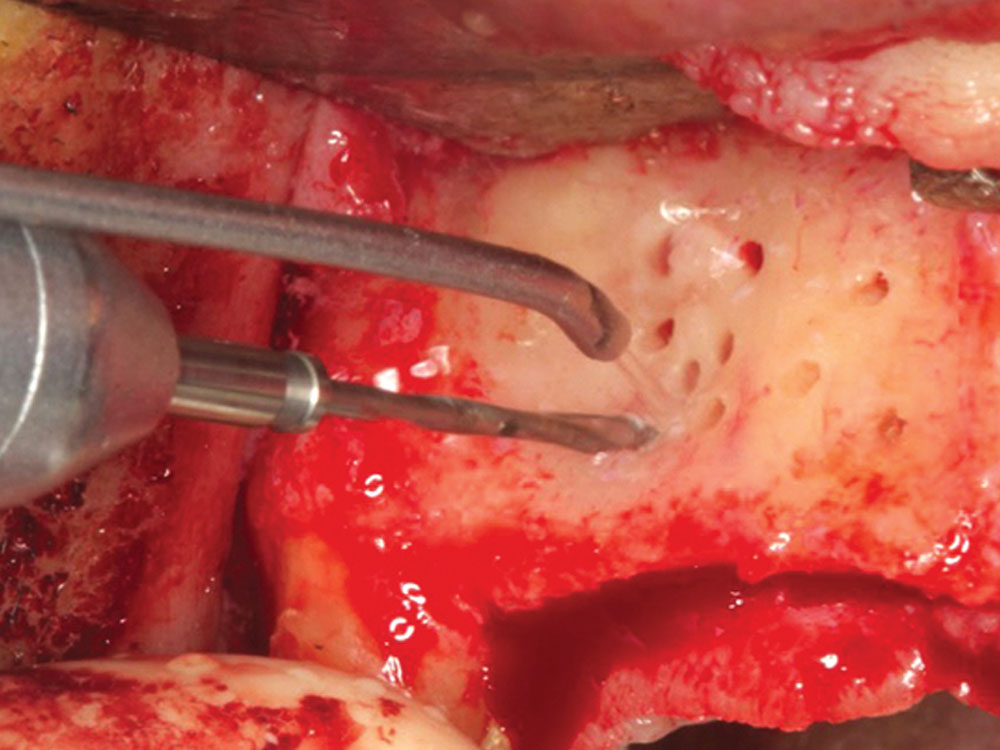

The decortication of the recipient site includes creating pilot holes into the cortical bone, which initiates the regional acceleratory phenomenon (RAP). RAP is the cellular process that stimulates and accelerates the healing rate of a graft site.5 Placing pilot holes into the cortical bone acts as a “noxious stimulus,” and the healing rate of a decorticated graft site has been shown to increase 2–10 times the normal healing rate.6 The holes create an open pathway to the underlying trabecular bone, where blood flow into the graft site will increase revascularization (angiogenesis) and allow for bone growth factors to readily enter the graft site. This acceleration is accomplished by the introduction of platelets to the area, which degranulate and release growth factors, including platelet-derived growth factor (PDGF) and transforming growth factor (TGF). The decortication process may be accomplished with the use of cross-cut fissure burs or small round burs that are used to perforate the cortical plate. Copious amounts of chilled saline should be used to prevent thermal trauma (Fig. 10).

Decortication holes with a cross-cut fissure bur

Figure 10: Decortication holes with a cross-cut fissure bur leading to the initiation of the RAP, allowing for faster and more predictable healing.